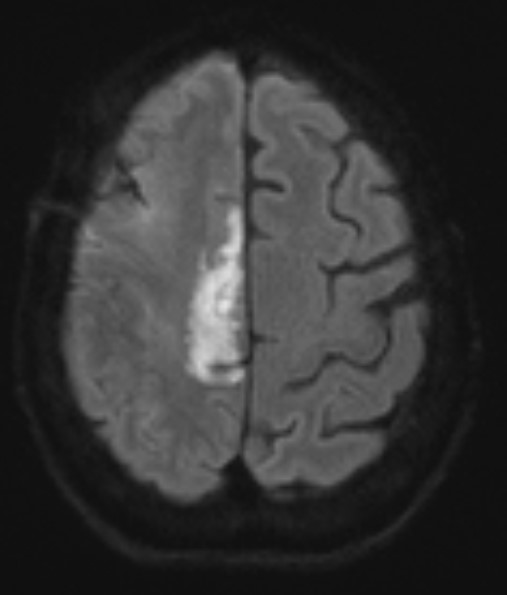

A 79-year-old right handed woman presented to a local hospital with left hemiparesis affecting her upper and lower extremities with mild left facial weakness for the last 2 weeks. She had a longstanding history of RA and had been off immune suppressant therapy for a few months due to improvement in symptoms. She had previously been on methotrexate and adalimumab in the past. She was evaluated with imaging and lumbar puncture (LP) at the time. MRI brain showed a semi-enhancing lesion over the right frontal lobe near the motor cortex with meningeal enhancement (Figure 1). CSF studies showed elevated protein at 65 and pleocytosis with WBC count of 47, 80% lymphocytes. CSF infectious panel was negative, but serum HSV-1 was positive. She reported a cold sore around this time as well. She was treated with broad spectrum antibiotics and acyclovir for 2 weeks. Infectious workup was otherwise negative. She did not have much improvement in her symptoms and was presented to our hospital 3 weeks later. Repeat CSF evaluation showed protein of 70 along with pleocytosis of 33 white blood cell (WBC), 75% lymphocytes. She received treatment with extended broad-spectrum antibiotics for 2 weeks. Rheumatological evaluation was negative for other signs of active RA. EEG showed bitemporal slowing with some quasi-periodic activity over the right temporal regions. She had some left arm shaking as well and was placed on levetiracetam for seizure prophylaxis. She did not have much improvement in her symptoms. A brain biopsy was performed which showed histopathological findings consistent with granulomatous inflammation confirming a diagnosis of RM (Figures 2-4). Labs showed highly elevated rheumatoid factor (RF) (>320) and anti-cyclinolytic citrullinated peptide (CCP) antibodies (>250). Rheumatology was consulted again and recommended high dose therapy with intravenous methylprednisolone for 5 days followed by resumption of immune modulating therapy. She developed a small right frontal ischemic stroke as a resultant of vasculitis from RM which caused exacerbation of left lower extremity weakness (Figure 5). She is kept on aspirin 81 mg daily for maintenance therapy for stroke prevention and levetiracetam for seizure prophylaxis along with daily prednisone and rituximab maintenance therapy for management of her RA / RM from rheumatology. She continues to work with physical therapy for her left hemiparesis which has shown some improvement. She sees rheumatology and neurology for continued follow up.

Figure 1. MRI brain showing right frontal lesion with cerebral edema and meningeal involvement.